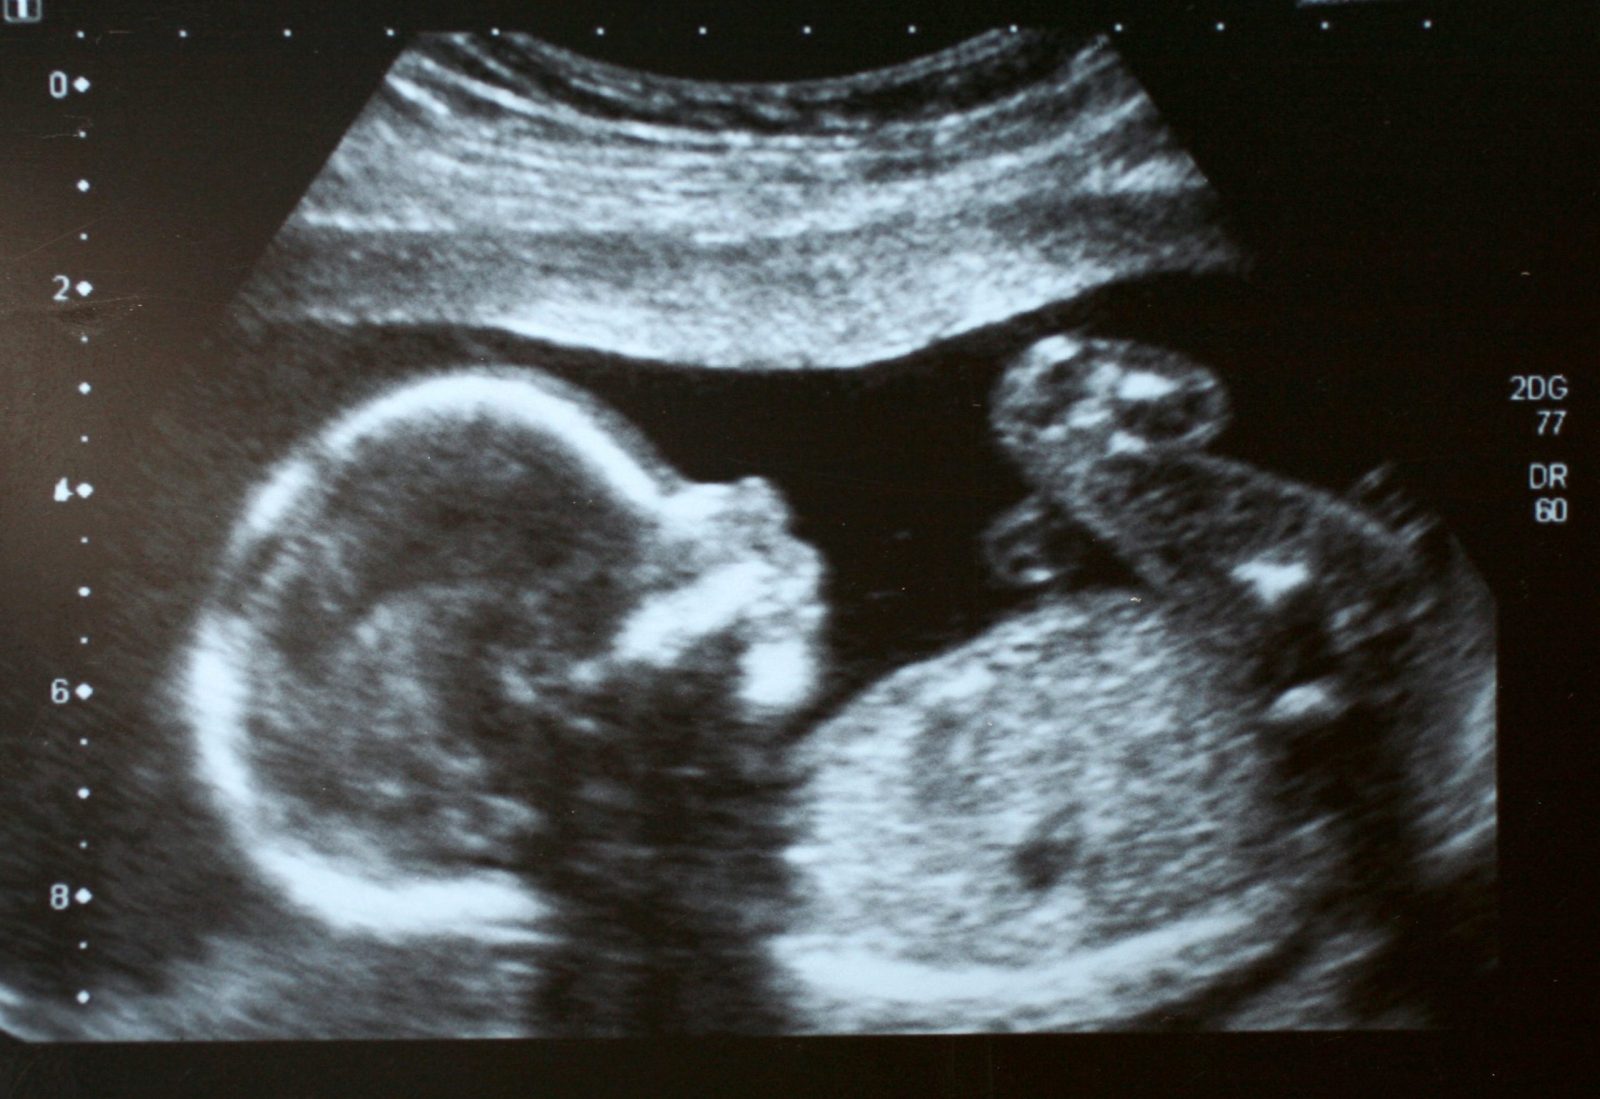

Une échographie de grossesse utilise des ondes sonores pour créer une image de votre bébé dans votre ventre. L’image sera affichée sur un écran que vous pouvez voir. La plupart des échographies de grossesse sont effectuées par un professionnel de la santé qualifié, appelé échographiste. Ces échographies sont indolores et ne présentent aucun risque pour vous ou votre bébé.

La plupart des échographies effectuées après 10 semaines de grossesse se font à travers l’abdomen. L’échographiste placera un gel sur votre ventre et frottera un appareil portable appelé transducteur sur votre ventre pour obtenir une image de votre bébé à naître.